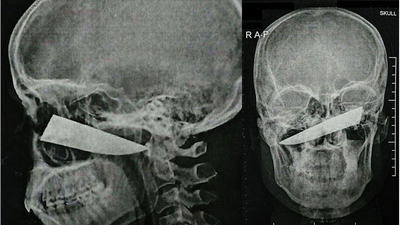

Yüzünden bıçaklanan adamın taramalardaki görüntüsü dudak uçuklattı. Kafatasına 10 santimlik bıçak saplanan ismi açıklanmayan adam, hayata tutunmayı başardı.

Taramalar, bıçağın burnun arkasından, kafanın derinliklerine doğru nüfuz ettiğini gösterdi. Uzmanlar, bıçağın kemiğe saplanıp kaldığını, ancak şanslı olan hastanın ciddi bir hasar almadığını söyledi.

25 yaşındaki hastanın kafatasına saplanan bıçak başarılı bir operasyonla çıkarıldı.